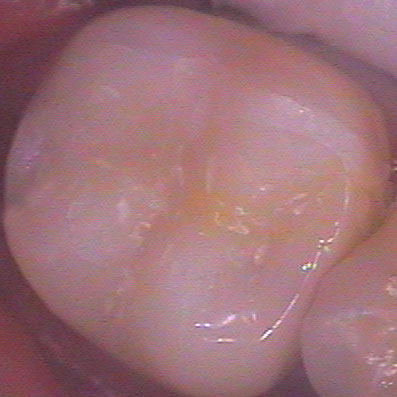

На снимката горе е показан предишният случай, заснет в по-близък план. Зъботехникът се е постарал да осигури добър оклузален моделаж. Механичната здравина при композитните вставки значително надвишава тази на директните възстановявания. Същевременно керамичните и металните вставки са още по-здрави от композитните. Първенец по отношение на механичната здравина е металната вставка. За съжаление тя е на последно място по естетика - повечето пациенти възприемат крайно негативно металния блясък на този вид конструкции. Тъй като зъботехникът изработва вставката върху гипсов модел, в случая формата на зъба с неговия екватор и контактни точки може да бъде възпроизведена много по-прецизно, отколкото зъболекарят може да извърши при клинични условия. Изработват се изпъкнали и широки екватори, които защитават зъбния венец от механични травми от храната и в същото време изпълват междузъбните амбразури, което предпазва от задържането на хранителни остатъци.